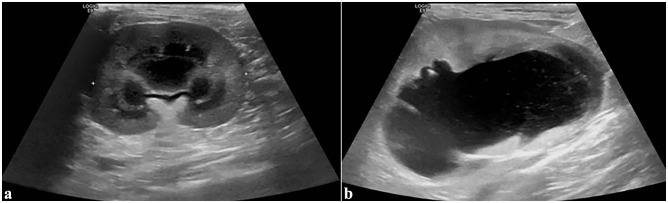

病例摘要:患者是一只 5.5 岁的雄性阉割短毛猫,两年前开始出现进行性慢性肾病。腹部超声波检查发现双侧慢性肾脏变性、肾结石、皮质高回声和梗死。使用 Synovis 血管耦合系统对肾动脉和静脉进行端对端吻合,进行了左侧正位肾移植。移植两个月后,肾脏数值升高,腹部超声波检查发现移植肾肾积水和肾积脓。透视前行肾盂造影发现近端输尿管狭窄。对其进行了近端新输尿管囊肿切除术,术后肾脏数值恢复正常。12 个月后,该猫因急性绞窄尿和严重氮质血症接受了重新评估。对比增强 CT 显示移植肾出现严重肾积水,近端输尿管阻塞,膀胱粘连。经探查发现,腹膜后纤维化覆盖了移植肾。考虑到临床情况,患者被放置了皮下输尿管旁路装置(SUB)。每隔 1-3 个月对临床病理分析、环孢素谷值、需氧尿培养和移植肾的超声波评估进行一次监测。每 3-6 个月重新评估一次 SUB 的通畅性。放置 SUB 15 个月后,由于膀胱造口导管扭结,SUB 出现闭塞,因此进行了更换。放置 SUB 后 28 个月,该猫的肾功能和临床状况恶化,最终安乐死:据作者所知,这是首次报道使用 SUB 装置治疗猫移植肾的输尿管梗阻。

Case summary: A 5.5-year-old male neutered domestic shorthair cat was presented with a 2-year history of progressive chronic kidney disease. Abdominal ultrasonography revealed bilateral chronic renal degeneration, nephrolithiasis, cortical hyperechogenicity and infarction. Left orthotopic renal transplantation was performed using the Synovis vascular coupling system for end-to-end anastomosis of the renal arteries and veins. Two months after transplantation, renal values were elevated, and abdominal ultrasonography revealed hydronephrosis and hydroureter of the transplanted kidney. Fluoroscopic antegrade pyelography identified a proximal ureteral stricture. Proximal neoureterocystostomy was performed and renal values normalized postoperatively. The cat was re-evaluated for acute stranguria and severe azotemia 12 months later. Contrast-enhanced CT revealed severe hydronephrosis of the transplanted kidney, obstruction of the proximal ureter and adhesions to the urinary bladder. Upon exploration, retroperitoneal fibrosis was found covering the transplanted kidney. Given the clinical situation, a subcutaneous ureteral bypass device (SUB) was placed. Clinicopathologic analyses, trough cyclosporine levels, aerobic urine cultures and ultrasonographic evaluations of the transplanted kidney were monitored every 1-3 months. Patency of the SUB was reassessed every 3-6 months. At 15 months after placement, the SUB occluded due to kinking of the cystostomy catheter and was replaced. At 28 months after SUB placement, renal function and clinical status deteriorated, and the cat was euthanized.